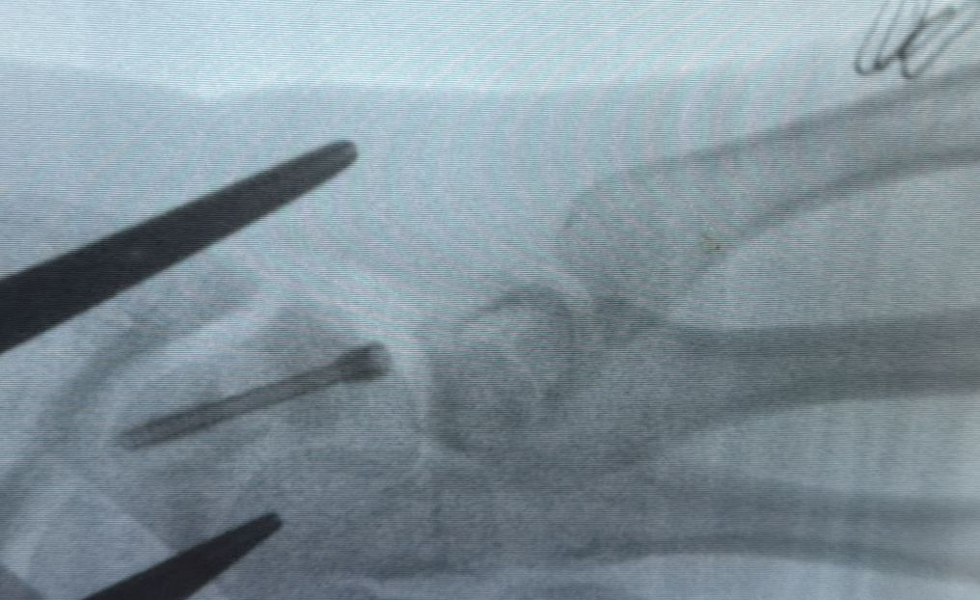

Adolescent operat pentru o fractură severă de os scafoid, cu deficit de consolidare (pseuodoartroză)

Caz medical rar în ortopedia pediatrică pe final de an

Un adolescent de 16 ani, din județul Bihor, a fost operat la Spitalul Clinic Județean de Urgență Bihor, pentru o afecțiune extrem de rară a încheieturii mâinii, apărută în urma unui accident sportiv suferit în timpul unui joc de fotbal în urmă cu un an. La aproape un an de la traumatism, persistența durerii și limitarea funcției mâinii au impus trimiterea pacientului dintr-o altă unitate spitalicească pentru tratament chirurgical de specialitate.

La 11 luni de la accident, pacientul prezenta dureri importante la nivelul articulației radio-carpiene, cu limitarea severă a mișcărilorscăderea forței mâinii drepte și imposibilitatea de a-și îndoi încheietura. În urma investigațiilor imagistice (RMN, radiografii) și a consulturilor de specialitate, medicul curant, Dr. Alexandru Pîrvan a diagnosticat pacientul cu fractură de os scafoid drept, cu deficit de consolidare, evoluată către pseudoartroză, asociată cu ruptură parțială a ligamentului scafo-lunar.

Pacientul a fost programat pentru intervenție chirurgicală, care a avut loc în ultimele zile ale anului 2025. Operația a constat într-o incizie de aproximativ 5 cm, cu curățarea focarului de pseudoartroză la nivelul osului scafoid și stabilizarea fracturii prin montarea unui șurub Herbert, utilizând o tehnică chirurgicală specială. Acest tip de șurub se remarcă prin faptul că nu necesită extragere ulterioară, fiind conceput fără vârf, el rămâne in corp și după ce osul s-a vindecat.

Durata intervenției a fost de aproximativ 2 ore și jumătate iar evoluția post-operatorie a pacientului a fost favorabilă.

Adolescentul a fost diagnosticat și operat în cadrul Secției Clinice Chirurgie și Ortopedie Pediatrică, de către Dr. Alexandru Pîrvan - medic specialist ortopedie pediatrică, pregătit la Centre Hospitalier de Luxembourg (CHL) și București.

Din echipa operatorie au mai făcut parte Dr. Samuel Piu - medic rezident ortopedie pediatrică și Dr. Adriana Dobrescu, medic primar ATI, Secția Clinică ATI II.